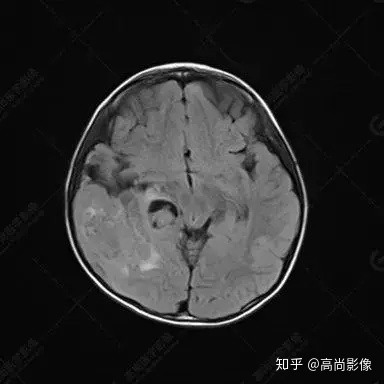

右側(cè)顳葉腫瘤切除術(shù)后(具體不詳):右側(cè)顳部骨質(zhì)不連續(xù)呈術(shù)后改變,右側(cè)顳葉術(shù)區(qū)見片狀長T1長T2信號(hào)影,F(xiàn)LAIR呈低信號(hào);術(shù)區(qū)后方右側(cè)顳枕葉見一巨大占位性病變影,邊界欠清,大小約6.2×5.8×4.3cm(前后×左右×上下),信號(hào)不均勻,T1WI呈等稍低信號(hào)間雜少許高信號(hào),T2WI呈高稍低混雜信號(hào),DWI示部分病灶彌散受限,相應(yīng)ADC圖減低,磁敏感序列見部分呈極低信號(hào),增強(qiáng)掃描可見明顯不均勻強(qiáng)化,鄰近硬腦膜及小腦幕增厚并明顯強(qiáng)化;另延髓右前方及右側(cè)橋小腦角區(qū)見一不規(guī)則形異常信號(hào)影,大小約3.2×1.3×3.7cm(左右×前后×上下),呈長T1稍長T2信號(hào),F(xiàn)LAIR呈等信號(hào),DWI未見受限,增強(qiáng)后明顯均勻強(qiáng)化,鄰近腦膜明顯強(qiáng)化。鄰近腦實(shí)質(zhì)及右側(cè)顳角明顯受壓;左側(cè)大腦半球未見局灶性信號(hào)異常,中線結(jié)構(gòu)稍左移。

右側(cè)顳葉腫瘤切除術(shù)后:現(xiàn)術(shù)區(qū)后方右側(cè)顳枕葉及延髓右前方占位,右側(cè)顳枕部硬腦膜及小腦幕明顯強(qiáng)化,結(jié)合既往影像資料,考慮為胚胎源性惡性腫瘤,如非典型畸胎樣/橫紋肌樣瘤(AT/RT)或原始神經(jīng)外胚層腫瘤(PNET)。

非典型畸胎樣/橫紋肌樣瘤(AT/RT) 是一種高度惡性中樞神經(jīng)系統(tǒng)腫瘤,臨床罕見,臨床表現(xiàn)無特異性,好發(fā)于 5 歲以下兒童,尤以 3 歲以下多見,在兒童原發(fā)性中樞神經(jīng)系統(tǒng)(CNS)腫瘤中占 1%~3%。該腫瘤體積一般較大,幕上大于幕下,有明顯的占位效應(yīng)。該腫瘤成分復(fù)雜,囊變、出血、壞死常見。因此 AT/RT信號(hào)混雜,囊性部分呈 T1WI低、T2WI高信號(hào),增強(qiáng)后不強(qiáng)化;若瘤體出血,囊內(nèi)可見T1WI稍高信號(hào)、T2WI低信號(hào),實(shí)性部分在 T1WI上呈混雜等、低信號(hào),在T2WI 及 T2-FLAIR上呈混雜等高信號(hào),增強(qiáng)掃描后大部分呈環(huán)形條帶樣明顯強(qiáng)化,中心壞死區(qū)不強(qiáng)化。另外,該腫瘤實(shí)性成分在DWI上呈高信號(hào),說明腫瘤細(xì)胞核密集,水分子擴(kuò)散明顯受限,提示該腫瘤惡性程度高,容易復(fù)發(fā)及轉(zhuǎn)移。